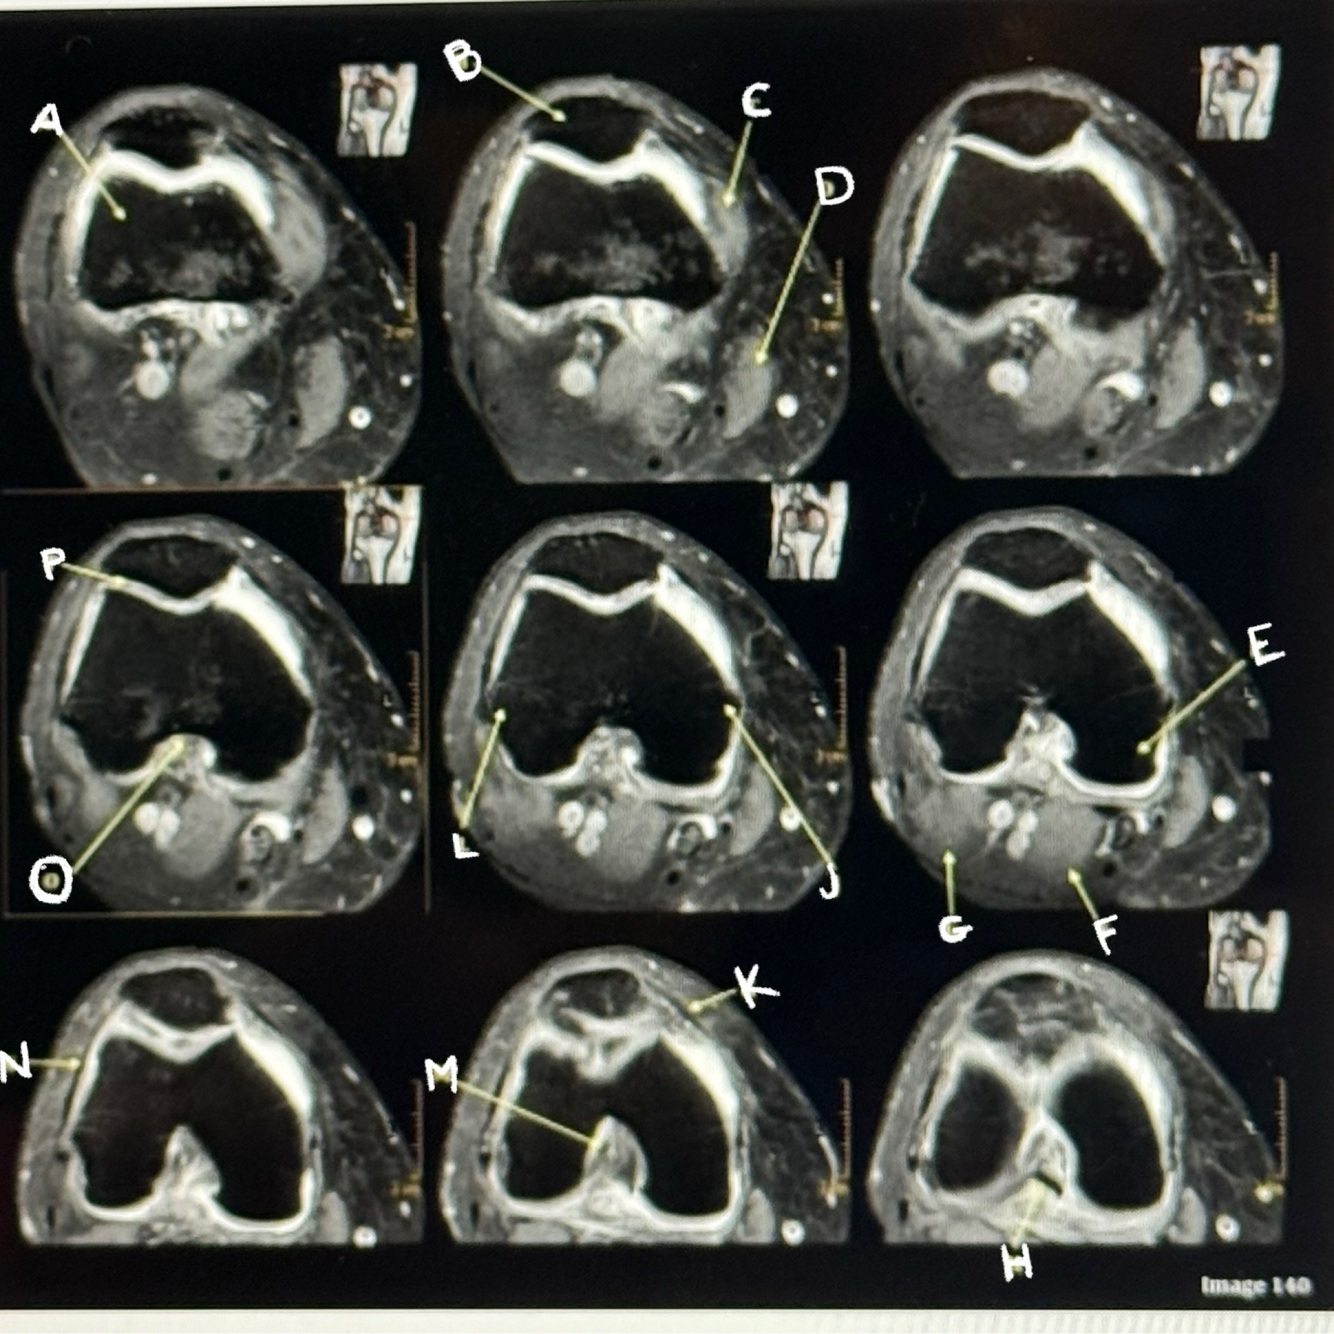

Q

Letter C points to the

A

Vastus medialis muscle

Letter D points to the

Sartorius muscle

3

Letter E points to the

Medial condyle

How well did you know this?

1

Not at all

2

4

5

Perfectly

Letter F points to the

Medial head gastrocnemius

Letter P points to the

Articular cartilage

39

Letter M points to the

Anterior cruciate ligament

40

Letter N points to the

Lateral retinaculum

41

Letter O points to the

Intercondylar fossa

42

Letter K points to the

Medial retinaculum

43

Letter L points to the

Lateral epicondyle

44

Letter H points to the

Posterior cruciate ligament (PCL)

45

46